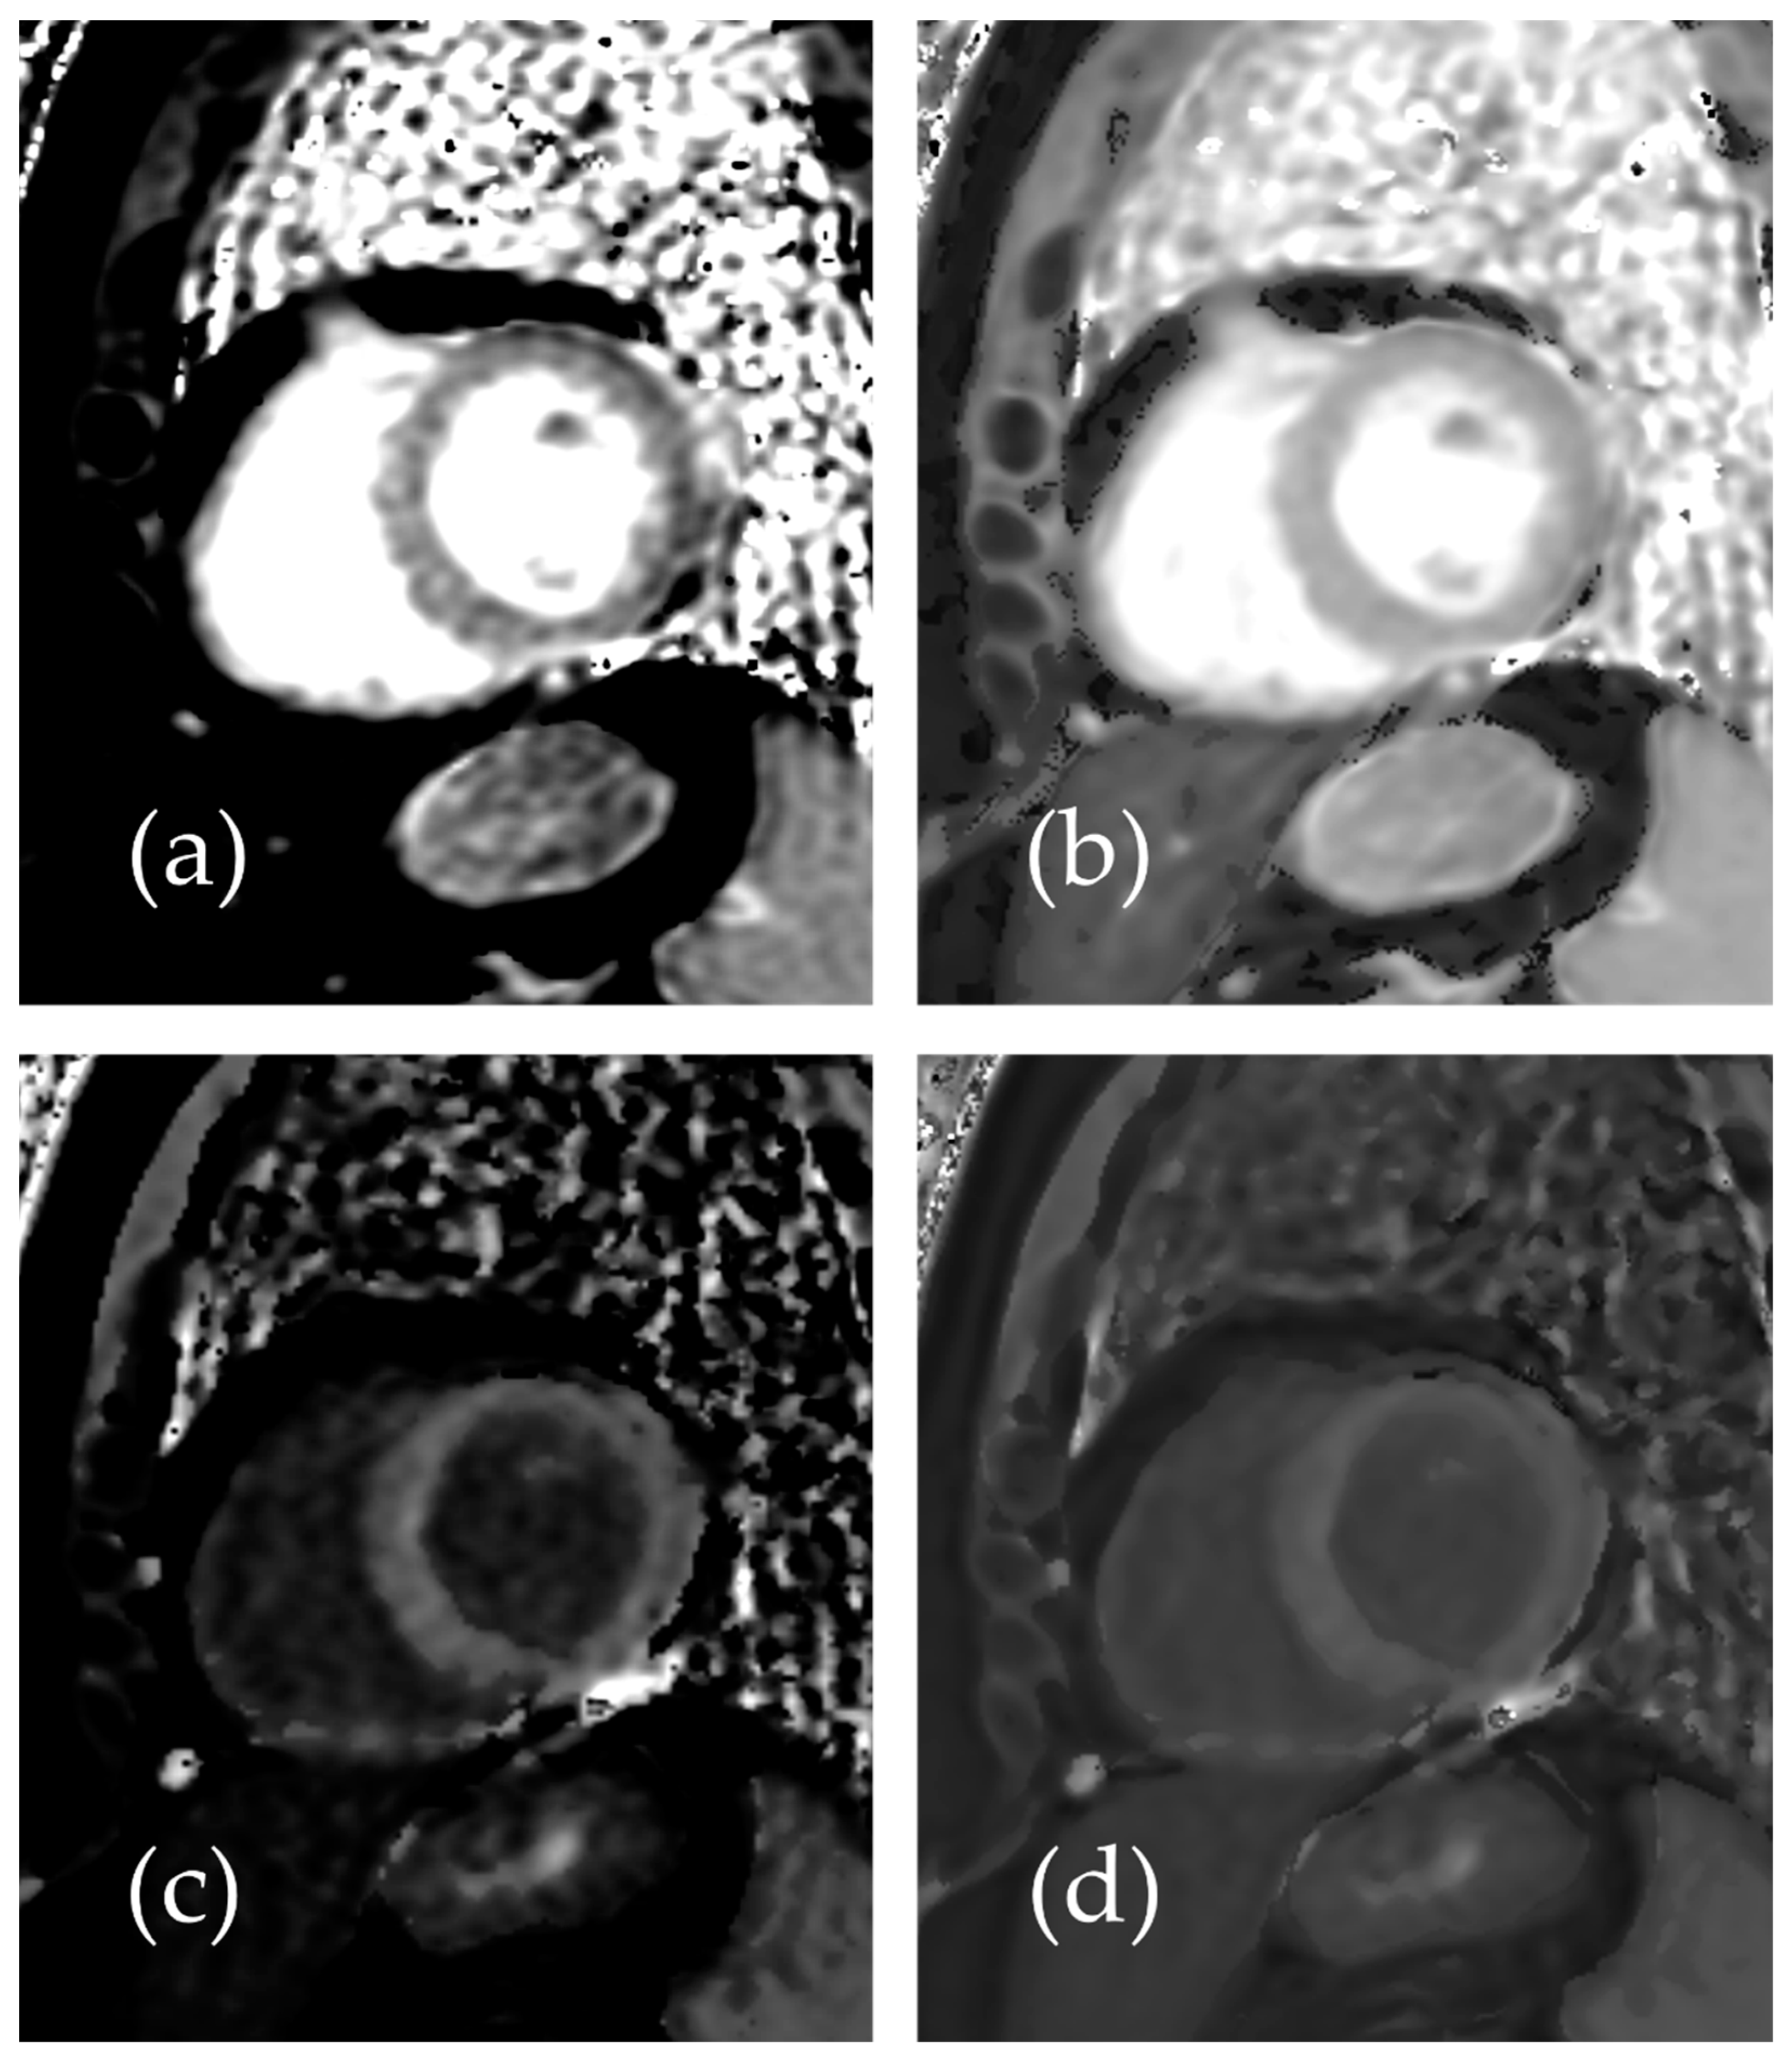

Representative native and post-contrast T1 maps illustrating the image quality without and with SR-DLR are shown in Figure 3. In the patient study, the ICCs for the mean native T1 values after the adaptation of SR-DLR were 0.822 (95% CI: 0.605–0.925), while the post-contrast mean T1 values had an ICC of 0.955 (95% CI: 0.891–0.982). Both were interpreted as excellent, demonstrating high agreement between observers. For the mean native T1 values, the median (IQR) was 1000.2 ms (974.3–1013.6) with SR-DLR and 1004.5 ms (977.2–1015.8) without SR-DLR (p = 1.000), showing no statistically significant difference. Post-contrast mean T1 values demonstrated a median (IQR) of 556.4 ms (536.4–592.7) without SR-DLR and 563.8 ms (537.1–591.7) with SR-DLR (p = 0.831), also showing no statistically significant difference (Table 2 and Figure 4). For native T1 values, the mean SD without SR-DLR was 44.0 ms (95% CI: 38.6–49.4) and with SR-DLR was 31.8 ms (95% CI: 26.9–36.7) (p = 0.001). For post-contrast T1 values, the mean SD without SR-DLR was 20.0 ms (95% CI: 17.2–22.4) and with SR-DLR was 14.4 ms (95% CI: 12.7–16.2) (p = 0.001) (Table 2 and Figure 5). The mean CV also decreased following SR-DLR application. For native T1 values, the CV decreased from 4.4% (95% CI: 3.9–4.9) without SR-DLR to 3.3% (95% CI: 2.8–3.8) with SR-DLR. For post-contrast T1 values, the CV decreased from 3.5% (95% CI: 3.1–4.0) without SR-DLR to 2.6% (95% CI: 2.3–2.9) with SR-DLR (Table 2).

Figure 3.

Representative images of a 54-year-old female patient with normal T1 mapping: (a) native T1 mapping image without SR-DLR, (b) native T1 mapping image with SR-DLR, (c) post-contrast T1 mapping image without SR-DLR, and (d) post-contrast T1 mapping image with SR-DLR. Images with SR-DLR (b,d) exhibit a lower noise level compared to those without SR-DLR (a,c).